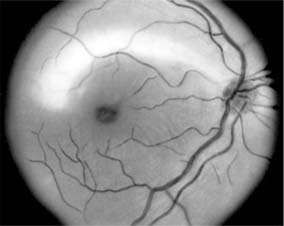

Figure 14-6

Figure 14-6: Examples of optic atrophy. Upper left: Primary optic atrophy due to nutritional amblyopia. Upper right: Secondary optic atrophy with retinochoroidal collaterals (arrows) due to optic nerve sheath meningioma. Lower left: Optic atrophy with optic disk drusen. Lower right: Pallor (atrophy) of right optic disk due to nerve compression by sphenoid meningioma. The left disk is normal.